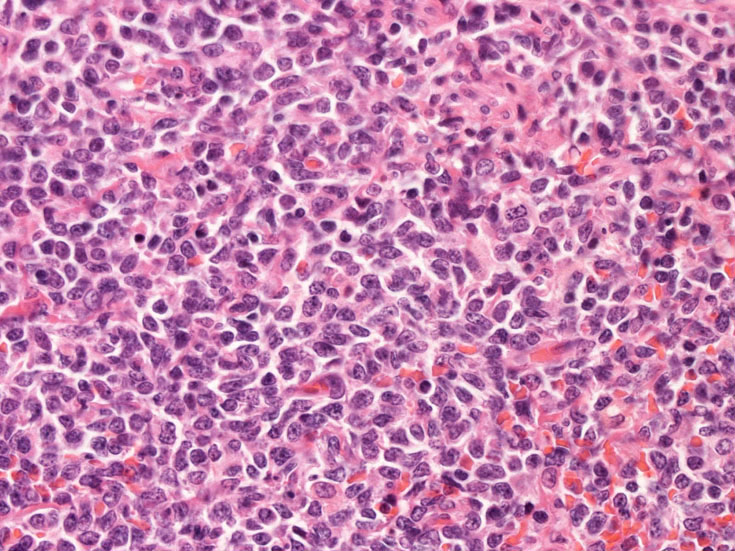

Fig04, Fig05は腫瘍細胞の拡大像。大型異型細胞の出現が認められる。腫瘍細胞はCD4+, CD56+, CD123+(Fig.06)

Fig.04Fig.05Fig.06 CD123